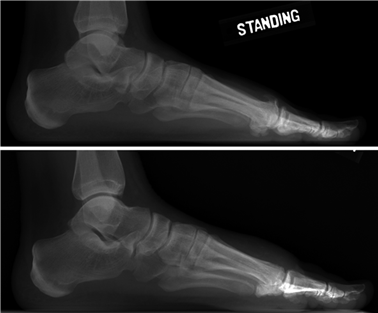

Weight-bearing anteroposterior (AP), lateral, and sesamoid axial radiographs are mandatory. On the AP view, the surgeon measures the Hallux Valgus Angle (HVA, normal < 15°), the Intermetatarsal Angle (IMA, normal < 9°), and the Distal Metatarsal Articular Angle (DMAA). The lateral view is scrutinized for Meary's angle (talo-first metatarsal angle) to identify midfoot collapse, as well as the presence of dorsal osteophytes indicative of hallux rigidus. The sesamoid axial view is critical for assessing the degree of sesamoid subluxation and the integrity of the crista.

Immediately post-operatively, the foot is placed in a bulky, compressive Jones dressing with a posterior splint to maintain the ankle in neutral and protect the forefoot. For distal osteotomies (e.g., Chevron), patients are typically allowed heel-touch or flat-foot weight-bearing in a rigid post-operative shoe. For proximal osteotomies or Lapidus arthrodesis, strict non-weight-bearing (NWB) with crutches or a knee scooter is traditionally mandated to prevent sheer forces across the fusion site. Elevation of the limb above the level of the heart is strictly enforced to minimize edema and promote wound healing. At the two-week mark, sutures are removed, and clinical alignment is assessed.

During this phase, patients transition to a Controlled Ankle Motion (CAM) boot. For distal osteotomies, progressive weight-bearing to tolerance is permitted. Crucially, active and passive range of motion (ROM) exercises of the first MTP joint are initiated to prevent capsular adhesions. The patient is instructed to manually plantarflex and dorsiflex the hallux multiple times daily. For Lapidus patients, NWB is generally maintained until 4 to 6 weeks, though recent literature utilizing robust plantar plating constructs has pushed for earlier protected weight-bearing. Radiographs are obtained at 6 weeks to assess for early callus formation and maintenance of alignment.